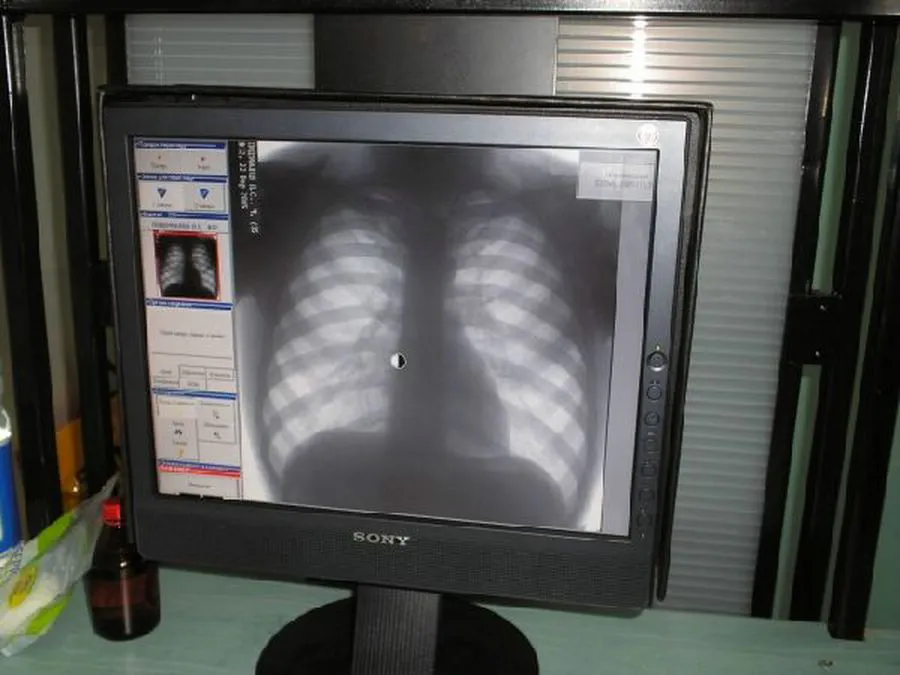

В Нижнекамске работал флюорографический кабинет на колесах

Передвижной пункт флюорографии работал 24 марта на центральном рынке. Сотрудники тубдиспансера подобную акцию проводят уже шестой раз. За несколько часов бесплатно и без очереди обследовались более 70 человек.

Профилактическая флюорография выявляет даже начальные патологические изменения. Ежегодно обнаруживается до 80 случаев туберкулеза, а также у 6% обследуемых -онкозаболевания легких и бронхов.